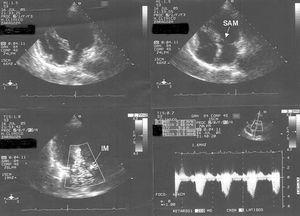

Otra de las hipótesis que explicarían esta patología es la existencia de anomalías en la arquitectura normal del miocardio. Así, Desmet4 y Kawai2 observan en algunos pacientes la presencia de un septo o «resalte» en la parte medial del tabique interventricular de morfología sigmoide (fig. 2), así como una orientación anormal en la inserción de la válvula mitral. Ambas variantes de la normalidad suceden con mayor frecuencia en mujeres y se cree que ante una intensa estimulación adrenérgica o una deshidratación condicionan un reducido volumen ventricular, predisponiendo a una obstrucción dinámica, grave y transitoria en el tracto de salida del ventrículo izquierdo (TSVI), al subdividir este ventrículo en 2 cámaras funcionalmente diferentes, con marcado aumento de la presión intraventricular en la pared ventricular distal de la cámara apical8,64-70. Dicha obstrucción provoca una isquemia subendocárdica secundaria a la reducción de la perfusión miocárdica, que no se corresponde a un territorio específico de una arteria coronaria, y que es el sustrato del aturdimiento miocárdico presente en este síndrome. Autores como Merli han podido demostrar estos hallazgos mediante el empleo de la ecocardiografía de estrés con dobutamina. Estas investigaciones revisten una gran importancia, ya que el tratamiento con nitratos podría aumentar dicho gradiente causando mayor deterioro, mientras que el tratamiento con bloqueadores beta, volumen, o estimulantes alfa-adrenérgicos sería beneficioso al reducirlo67,70.

Figura 2. Ecocardiograma transtorácico realizado en un plano apical de cuatro cámaras donde se aprecia la geometría del tracto de salida de ventrículo izquierdo (TSVI) con movimiento anterior sistólico de la válvula mitral (parte superior), insuficiencia mitral significativa y gradiente elevado en el TSVI (parte inferior).